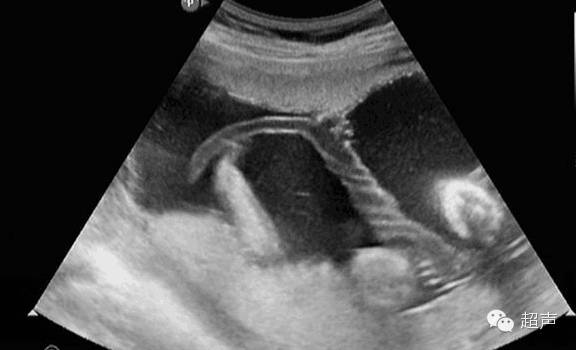

接下来讲讲帆状胎盘,帆状胎盘与正常胎盘的差别在于:脐带并不附着胎盘上,而是胎盘之外的胎膜上,那么这个时候脐带的血管分散成数条分支呈扇形分布走行,这些分支最终连于胎盘边缘部分,这些呈扇形分布的血管分支走行在羊膜和绒毛膜之间,形成一膜状结构,如帆船的帆布,故称帆状胎盘。由于这些血管分支的周围失去了正常的脐带结构,缺乏华通胶的支持,极易发生血管破裂,特别是当这些血管分支位于胎先露(分娩时最先进入骨盆入口的胎儿部分)下方,跨越或接近宫颈内口时,当血管受压或胎膜破裂时血管撕裂,可造成胎儿缺氧或急性失血,医学上称之为血管前置。这种出血属于胎儿出血,由于足月胎儿体内血容量约250ml,如失血量超过20%-25%(50 ~ 60ml),即可发生胎儿失血性休克,因此胎儿死亡率极高。

超声检查可以观察胎盘类型、位置、脐带附着于胎盘的部位,部分孕妇需经阴道超声检查的,还可以比较清楚的显示宫颈内口及其周围的结构、胎膜上前置血管的走行情况。